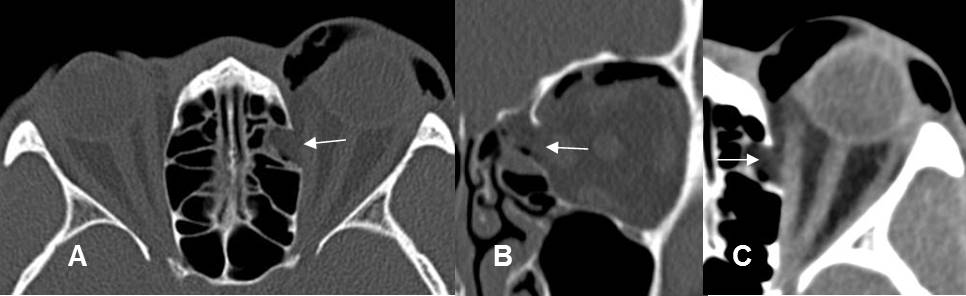

Fig 215 C. Fractura de órbita.

A: TAC axial y B: TAC reconstrucción coronal. Fractura en el borde interno de la órbita.

C: TAC axial en ventana de tejidos. Hay herniación de la grasa, pero permanece intacto el músculo recto interno.